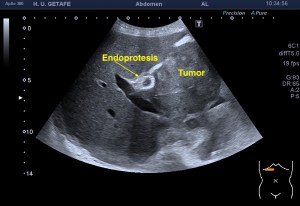

La imagen 3 y 4, como son tan nítidas, puedes ver como el quiste de Baker no es un quiste de Baker simple, la pared es grosera, tiene septos y ecoestrusturas que hacen pensar que el quiste ha podido sufrir algún sangrado. Hay que descartar la formación de lesiones sólidas o polos sólido en los quistes (usando doppler), por norma general, en todos aquellos quistes que estudiemos, en otras localizaciones, por ejemplo, en la mama, en el abdomen, etc.